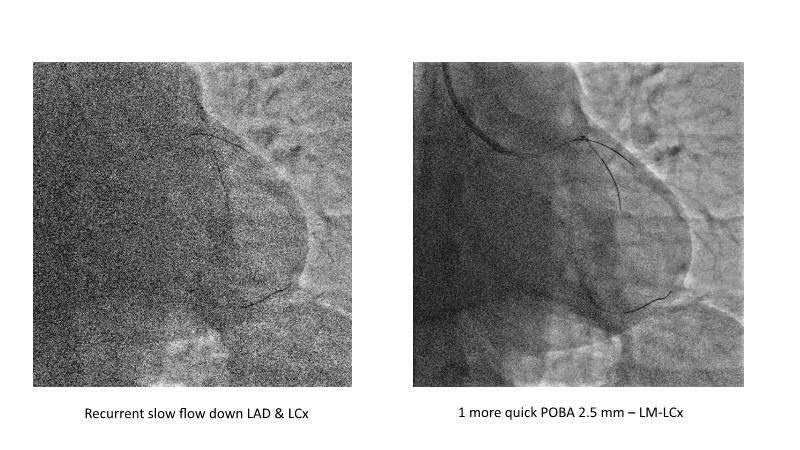

This session is recommended for you if you are seeking insights into the advantages of using IVUS imaging over visual assessment for better outcomes in left main bifurcation procedures. Discuss with experts the benefits of using RotaCUT in lesion preparation for left main bifurcation and explore the impact of high radial strength stents on the procedure's success.

• To see advantages of RotaCUT as part of lesion preparation in left main bifurcation